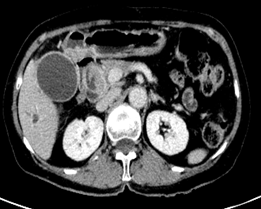

2.肝门型及远端型胆管细胞癌

病变区胆管壁增厚,管腔狭窄,伴上游胆管扩张。

•  CT:胆管浸润狭窄型胆管癌动脉期明显强化,外生型胆管癌门脉期强化更显著。

•  MRI:信号特征反应肿瘤组织成分,纤维成分越多,T2WI信号越低,粘液及坏死组织越多,T2WI信号增加,肿瘤无薄膜,增强呈渐进性强化。

肝内胆管细胞癌     肝外胆管细胞癌

病理提示①为肝内胆管细胞癌,②肝外胆管细胞癌